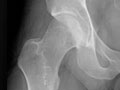

You may also have an X-ray (such as an X-ray of the hip or knee) or other imaging tests to check for joint damage.

This is done when other treatments haven't worked and damage to the joint can be seen on X-rays. It involves surgery to replace the ends of bones in a damaged joint. The surgery creates new joint surfaces. The joints that are replaced most often are the hip, knee, and shoulder. But other joints such as the elbow and the ankle can also be replaced.